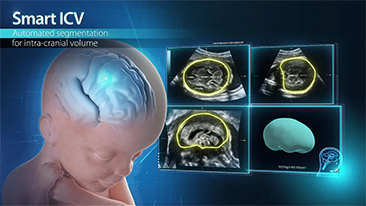

Didukung oleh platform ZST+ yang canggih, solusi cerdas yang lengkap dari Nuewa dirancang secara khusus untuk mendukung kesehatan kaum wanita yang lebih baik selama masa prakehamilan, kehamilan, dan pemulihan pascapersalinan, untuk menghasilkan diagnosis yang komprehensif dan efisien guna memenuhi tantangan klinis yang semakin meningkat.